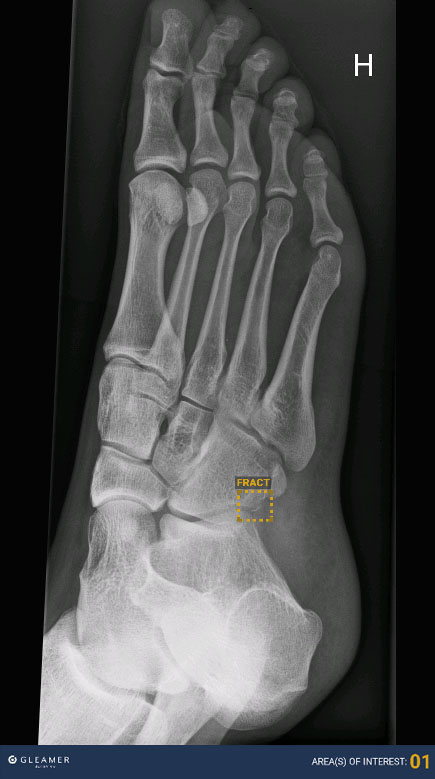

Den første applikasjonen som skal tas i bruk er en frakturløsning (Boneview) fra leverandøren Gleamer. Plattformen og applikasjonen er allerede installert, og det jobbes nå med å validere løsningen for å sikre at den leverer som antatt. Dersom resultatene er gode, planlegges det idriftsetting i august, deretter bredde til de andre sykehusene i Vestre Viken.

Bilde av den første foten som er analysert ved hjelp av kunstig intelligens.

Bilde av den første foten som er analysert ved hjelp av KI.